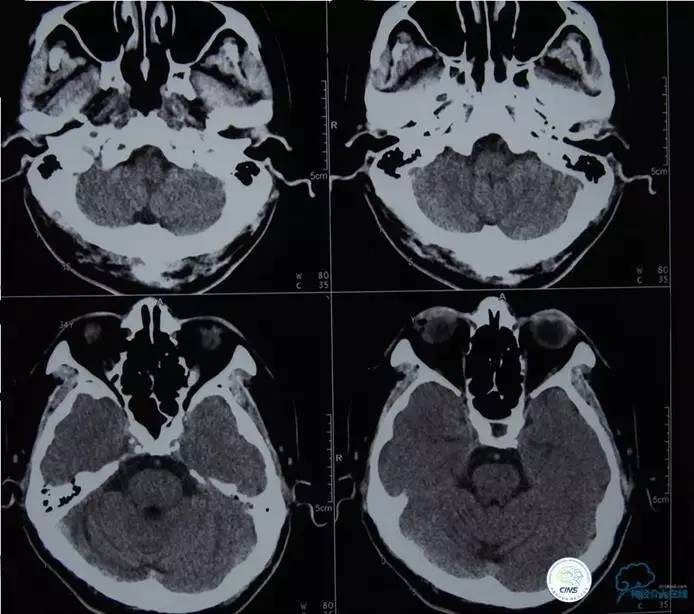

患者:徐XX,男,38岁,既往高血压病史1年。

现病史:患者2012年11月26日,2:00PM左右无明显原因出现头晕,不伴头痛,无视物成双,症状持续存在,无明显好转,遂到当地医院就诊,颅脑CT未见出血。5:50PM出现左侧肢体活动失灵,手脚不能活动,伴有左侧口角歪斜,无肢体抽搐及意识障碍,言语尚可。9:00PM左右到我院急诊室,述途中肢体一度恢复活动。

查体:两侧瞳孔等大等圆,对光反射灵敏。左侧肢体肌力2级。NIHSS评分8分,急诊查心电图、血常规、肝肾功、凝血四项、心肌酶等未见明显异常。急诊颅脑CT未见出血。

▼L-CCA

检查右侧肢体肌力,未见明显异常。

尿激酶20万单位,动脉导管内推注。

口服拜阿司匹林300mg,再次取栓。

2.0×15mm球囊扩张V4段狭窄。

Penumbra 导管再次取栓。

▼R-VA

▼第三天MRA